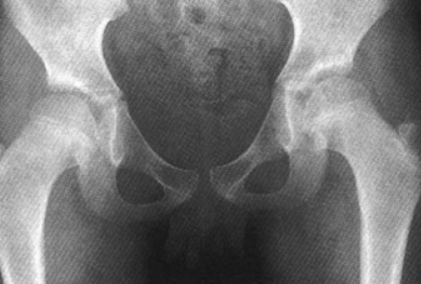

1招叫你鉴别全髋与半髋,如此简单!